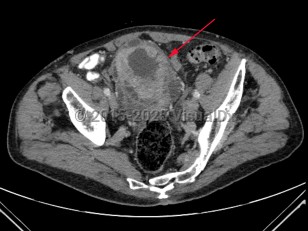

Imaging Studies image of Bladder cancer - imageId=7885454. Click to open in gallery.  caption: '<span>Axial image from an enhanced CT scan of the pelvis  demonstrating marked irregular wall thickening of the bladder.</span>'

Axial image from an enhanced CT scan of the pelvis demonstrating marked irregular wall thickening of the bladder.